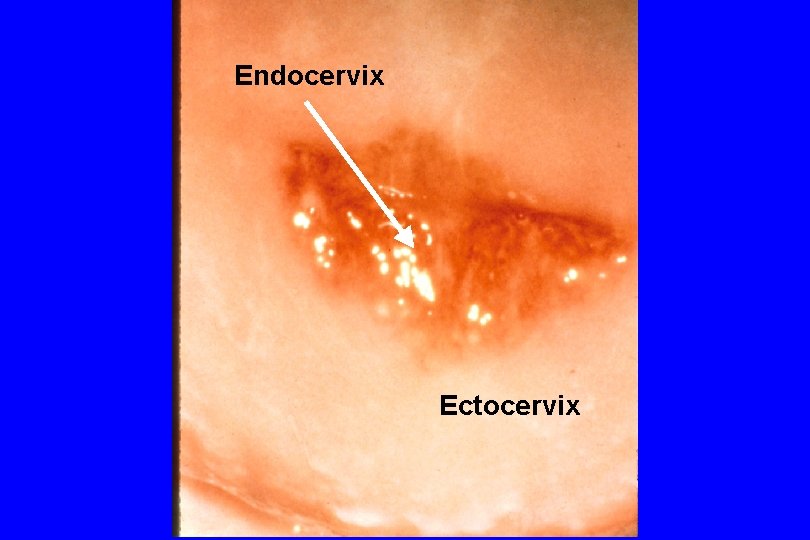

Endocervix Ectocervix

Cervical Anatomy and Terminology · · Ectocervix Endocervix Ectopy (“Ectropion”, “Erosion”) - Physiologic ectopy: Migration of endocervical mucosa onto the ectocervix ~menarche • Usually regresses age 17 -20 • Can recur during pregnancy or hormonal contraception • Probably one reason C. trachmatis is so strongly related to young age in women • Regression can generate nabothian cysts - Pathologic ectopy: Edema due to inflammation (cervicitis) results in eversion (“edematous ectopy”) Vagina has no mucus-secreting glands; presence of mucus in vaginal secretions denotes cervical origin